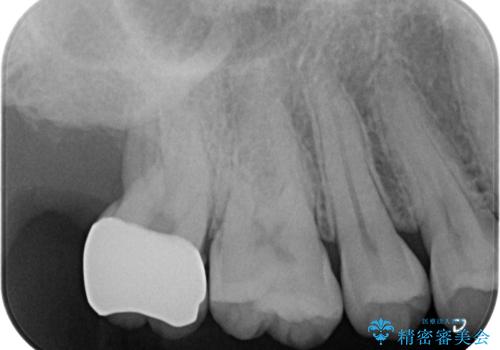

- 銀歯を白くしたいとのことで来院されました。

歯を覆っている銀の詰め物の面積が広く、セラミックで同じ形態にすると強度に不安が残るため被せ物での修復処置を行っていきます。

- 右上7 仮歯+ジルコニアクラウン:11,000円+121,000円費用は治療当時の料金となります

ブラッシングが上手な患者様であったため歯茎の締りもよく、大変適合の良い被せ物を装着することができました。